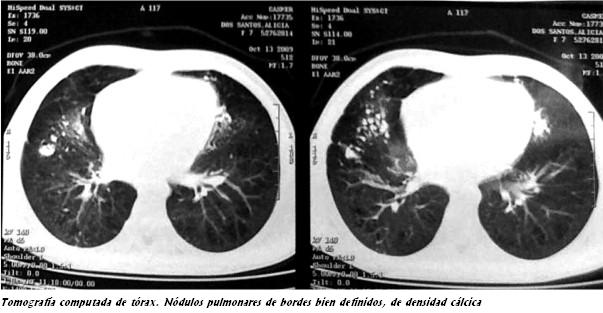

- Interrogatorio clínico adecuado, radiografía de tórax y tomografía computarizada de alta resolución (TCAR)